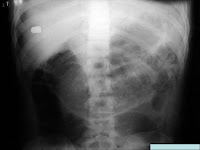

É uma especialidade que tem como finalidade o auxílio na Medicina Legal, baseado na realização de imagens radiológicas com a indicação na análise e investigação das causas de óbitos, sendo um estudo radiográfico pós-morte para a complementação das autópsias.

Algumas Imagens em Radiologia Forense: